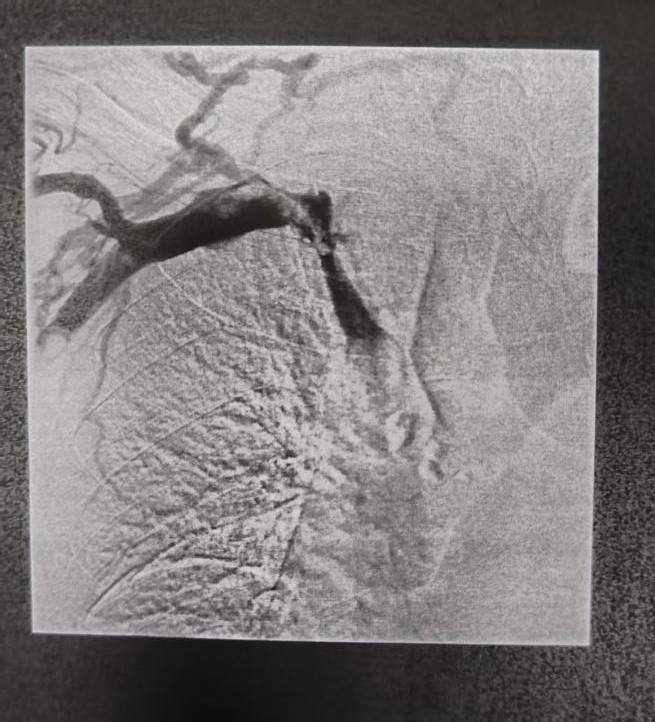

球囊扩张后放支架前

置入支架后

手术中,团队通过微创穿刺,成功将纤细的导管导丝通过闭塞段,随即运用球囊扩张技术重建血管通路,清除静脉内血栓,并精准置入支架以维持血管长期通畅。手术过程顺利,患者术后上肢肿胀迅速消退,恢复良好。